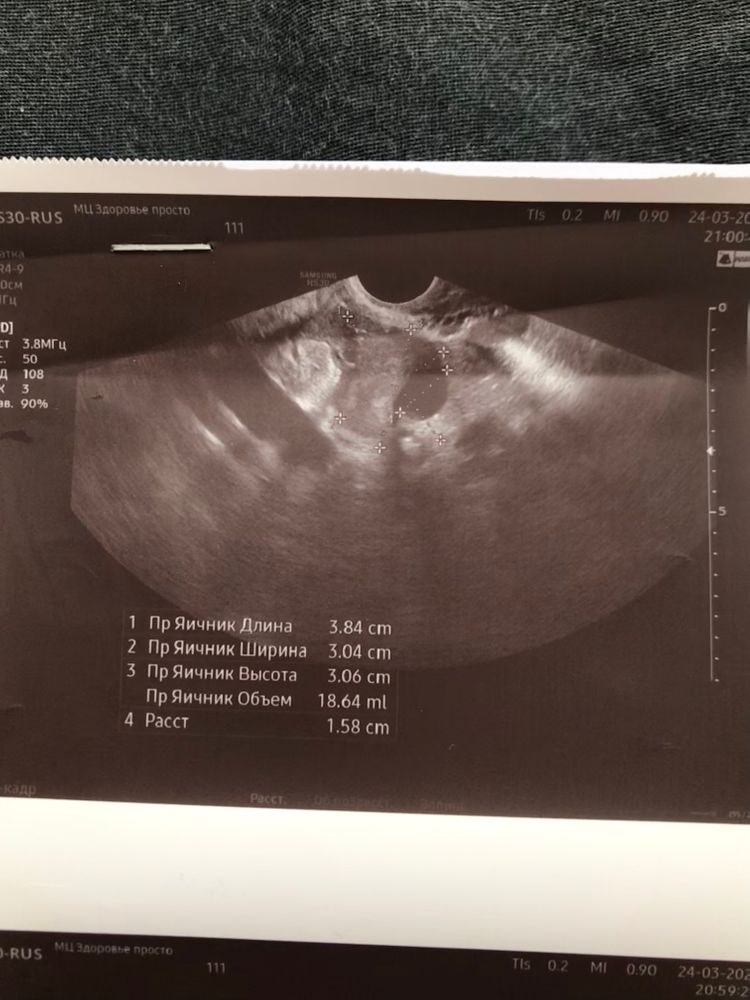

2 желтых тела или одно?

Фото правого и левого яичника